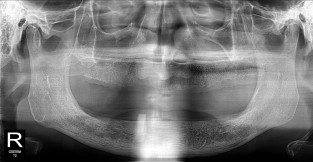

• 9

무치악

치료기간 : 2023-02-21 ~ 2023-10-21

1. 상기 x-ray 이미지 모두 동일한 해당 의료기관에서 진료한 환자입니다.

2. 상기 x-ray 이미지 모두 동일 인물의 것입니다.

3. 치료 전 이미지는 2023-02-21에 촬영했으며, 치료 후 이미지는 2023-10-21에 촬영하였습니다.

4. 상기 x-ray 이미지 모두 동일 조건에서 환자분의 동의를 받아촬영되었습니다.

* 임플란트 시술은 환자분의 상태(고혈압, 당뇨 등)에 따라 부작용이 있을 수 있으니, 반드시 전문의와 상담이 필요합니다.

* 임플란트 수술 부작용

: 수술 후 출혈, 교합, 통증, 붓기, 염증 등의 문제점이 발생할 수 있습니다.)